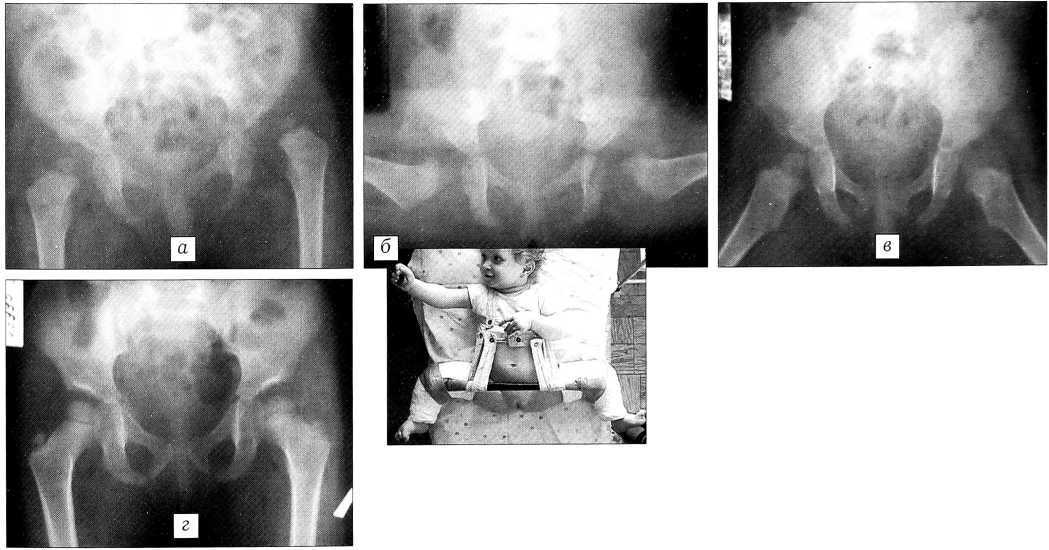

Больная М.,1 года. Диагноз: врожденный вывих бедра слева, подвывих справа. Вывихи выявлены в возрасте 5 мес, лечилась по месту жительства, без эффекта (рис. 1 ,а). В ЦИТО была наложена функциональная гипсовая повязка (рис. 1, б), производилась тракция. Через 2 нед вывихи устранены (рис. 1, в). В течение 6 мес осуществлялась иммобилизация гипсовыми повязками, а затем шинами Виленского. В этот период проводилось комплексное восстановительное лечение. Нагрузка на нижние конечности разрешена (в шинах) через 10 мес после вправления. Через 7 лет движения в тазобедренных суставах в полном объеме, суставы стабильны, длина нижних конечностей одинаковая. На контрольной рентгенограмме головки бедер центрированы во впадинах, покрытие головок полное (рис. 1, г).

Рис. 1. Больная М. 1 года. Диагноз: врожденный вывих левого бедра, подвывих правого бедра.

а — рентгенограмма при поступлении; б — лечение функциональной гипсовой повязкой по Тер- Егиазарову—Шептуну; в — рентгенограмма на этапе лечения; г — рентгенологический результат через 7 лет: ацетабулярный индекс 25°, угол Виберга 30°, коэффициент покрытия головки справа 1, слева — 0,9; д — функциональный результат через 7 лет: объем движений в тазобедренных суставах полный, симптом Тренделенбурга отрицательный с обеих сторон;